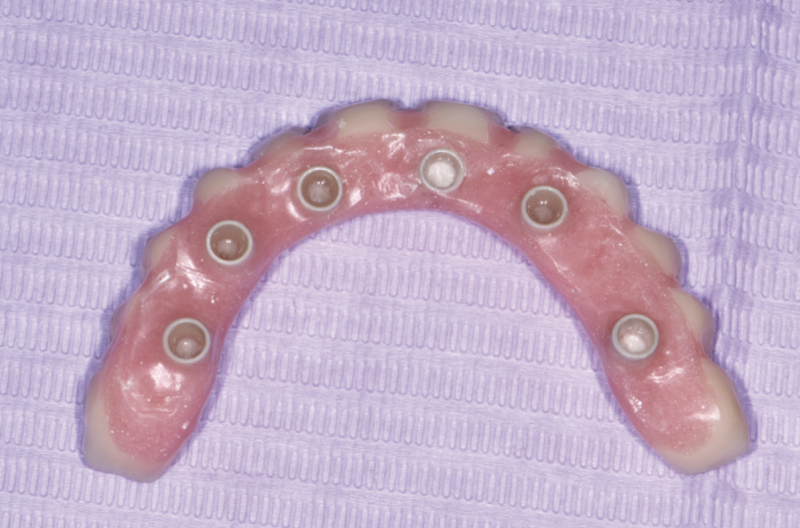

Ridge-side view of lower final prosthesis: note appropriate spaces for intraoral cementation of Fixed caps into the prosthesis

Ridge-side view of upper final prosthesis: note appropriate spaces for intraoral cementation of Fixed caps into the prosthesis